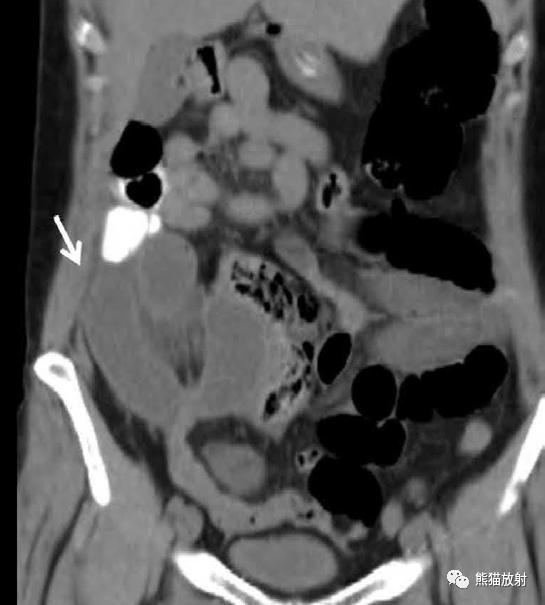

肠系膜疝。 扩张、充满液体的小肠襻丛位于前腹壁下的升结肠侧旁(箭),取代网膜脂肪。充盈的血管及邻近肠系膜模糊,反映了小肠绞窄性梗阻。